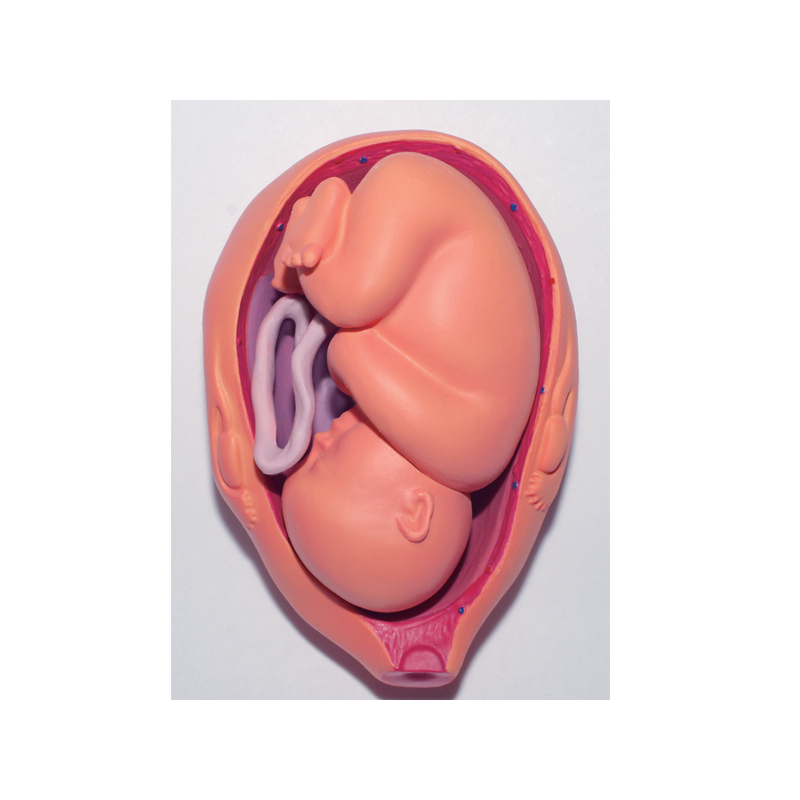

4D MASTER Human Anatomy Premium Embryo Development, Fertilisation to Fetus Development